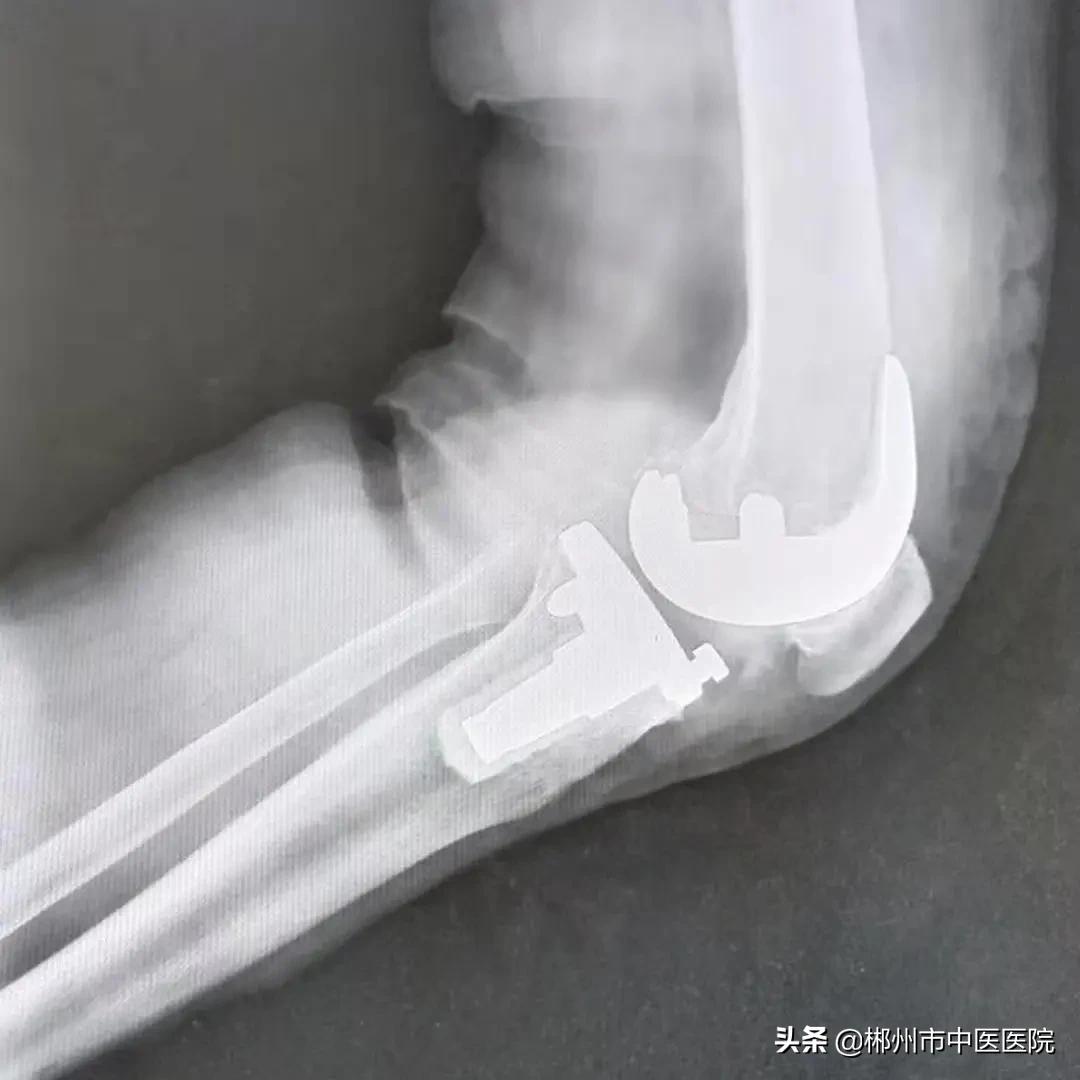

通过安装人工膝关节假体,解决了李奶奶膝关节内翻畸形问题,纠正了下肢力线。

术后X线片情况

术后第二天,李奶奶下肢屈曲可达120度,伸直0度,可辅助助步器下地行走,复查DR片显示膝关节假体间隙平衡。